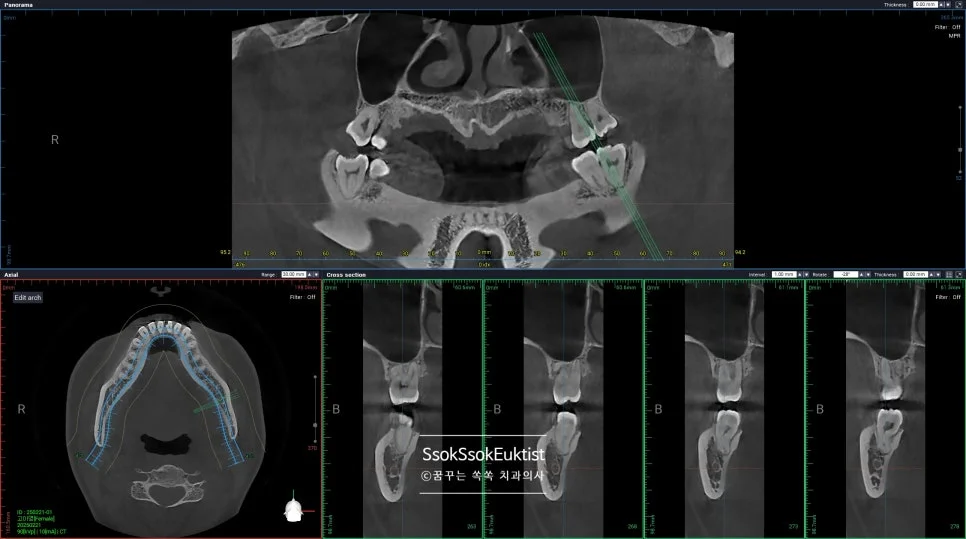

CBCT(3D CT)로 신경관 위치 확인

CBCT 우측 하악 매복 사랑니 신경관 근접도 분석

우측 CBCT — 신경관 근접도 분석

CBCT 좌측 하악 매복 사랑니 신경관 근접도 분석

좌측 CBCT — 신경관 근접도 분석

매복된 사랑니는, CT를 통해 신경관과 맞닿아 있진 않은지 정밀하게 분석 후 발치를 시도합니다.